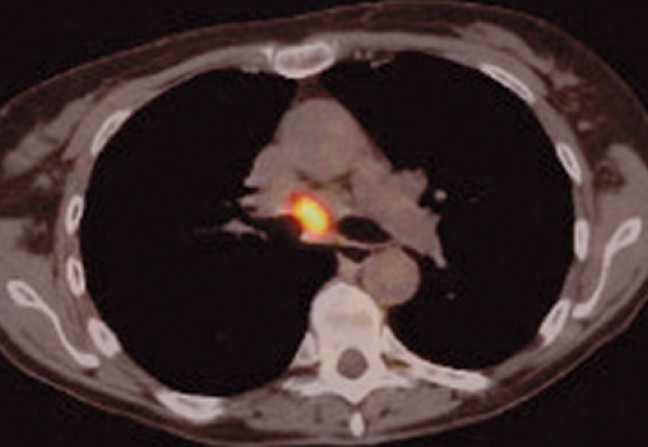

08Point formation n°8

Le scanner low dose est utilisé dans le cadre du dépistage du cancer bronchopulmonaire depuis les années 90. Auparavant, seule la radiographie thoracique standard était utilisée. Mais l’étude randomisée PLCO (2011), qui a porté sur plus de 150 000 participants, a mis en évidence que cet examen ne diminuait pas la mortalité spécifique comparé à l’absence de dépistage et n’était donc d’aucune utilité.

Le scanner low dose est apparu plus sensible. Mais il a fallu attendre l’essai NSLT en 2011, portant sur 53 000 patients asymptomatiques de 55 à 74 ans, fumeurs (ou anciens fumeurs sevrés depuis moins de 15 ans) avec un tabagisme supérieur à 30 paquets-années, pour prouver son efficacité. Il a montré que la mortalité spécifique était significativement réduite de 20 % (p = 0,004) ainsi que la mortalité générale, qui était aussi significativement réduite de 6,7 % chez les patients dépistés.

En outre, l’essai Nelson publié en 2020 a apporté des données supplémentaires. Il a été mené chez des fumeurs et anciens fumeurs de 50 à 74 ans dont le tabagisme devait être supérieur à 15 cigarettes par jour pendant plus de vingt-cinq ans ou à 10 cigarettes par jour pendant plus de trente ans. S’ils étaient anciens fumeurs, ils devaient avoir cessé leur tabagisme depuis moins de dix ans. Le scanner low dose était fait à T0, puis à 1 an, 3 ans et 5,5 ans. L’étude reposait sur l’évaluation du temps de doublement des nodules, ce qui a permis de limiter significativement le taux de faux positifs. Les résultats ont confirmé l’efficacité du dépistage, avec une réduction de la mortalité spécifique à dix ans de 24 % chez les hommes et 33 % chez les femmes (absence de significativité statistique).